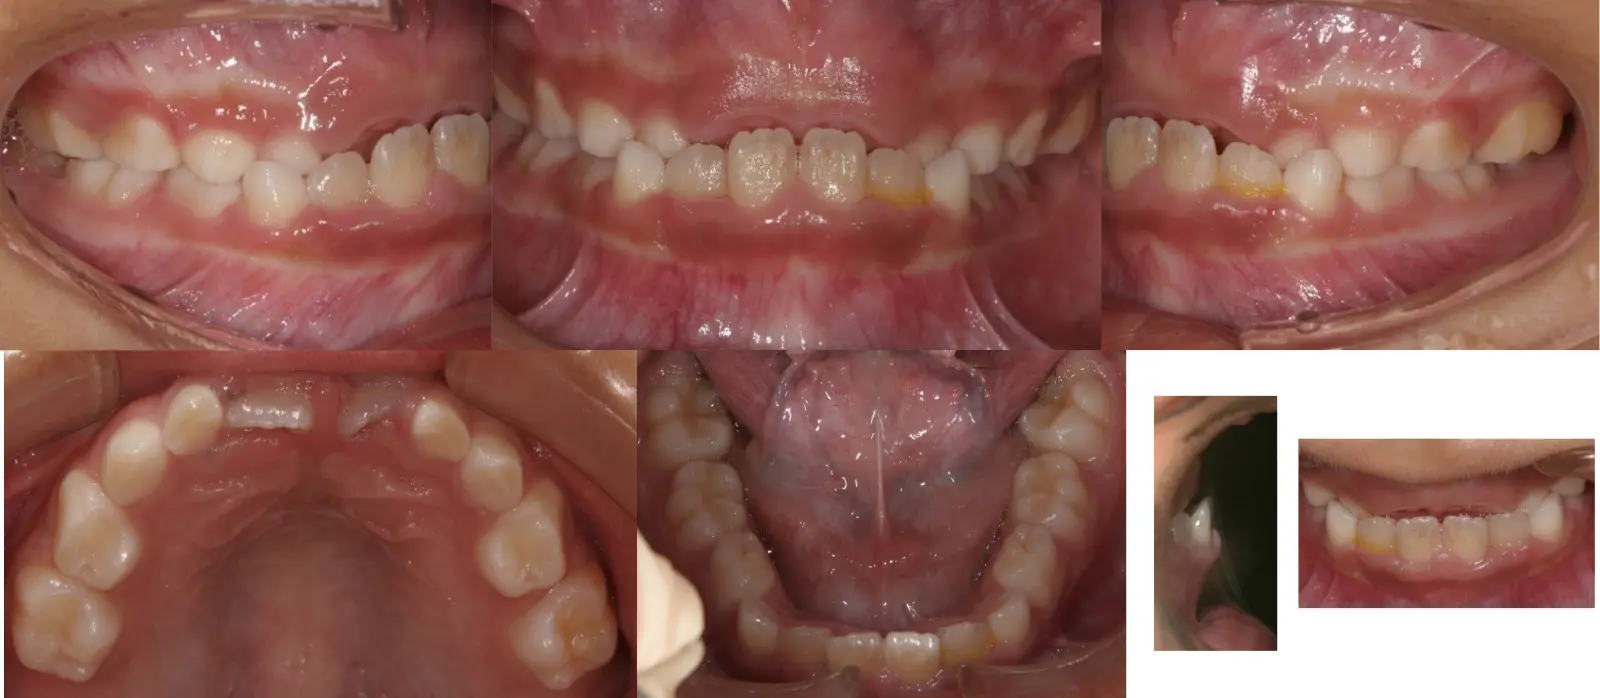

アングルⅡ級 叢生を伴う軽度上顎前突症

第一段階の治療のみで、

永久歯は問題なく萌出し、安定している

- 主訴

前歯のガタガタ

- 年齢

9歳

- 治療期間

10ヶ月

- 治療回数

10回

- 治療に用いた主な装置

拡大床、2by4

- 治療費

400,000円(税別)トータル料金

- 抜歯部位

非抜歯